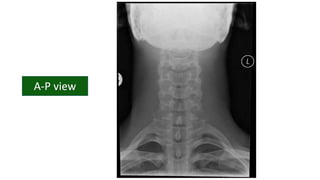

CERVICAL SPINE

PATHOLOGY

DR. PRAMOD NAGURE